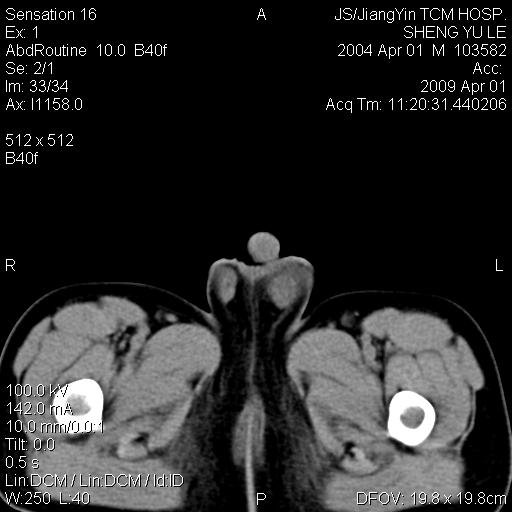

m,5岁。尿痛尿频数天。既往无病史。ct平扫腹盆腔积液。膀胱壁明显增厚。另可见心包增厚。wbc5万,骨髓穿等结果。请指教。

膀胱影像表现结合临床应该是急性膀胱炎症,但为什么有腹水呢?双肾输尿管无扩张,泌尿系压力应该不大不至于引起尿外渗,应该是腹膜感染引起的,但楼主没有提及相关症状,腹膜及膀胱结核?患者白细胞5万(结核不至于这么高啊),脾脏增大,是不是有白血病?进一步检查。。